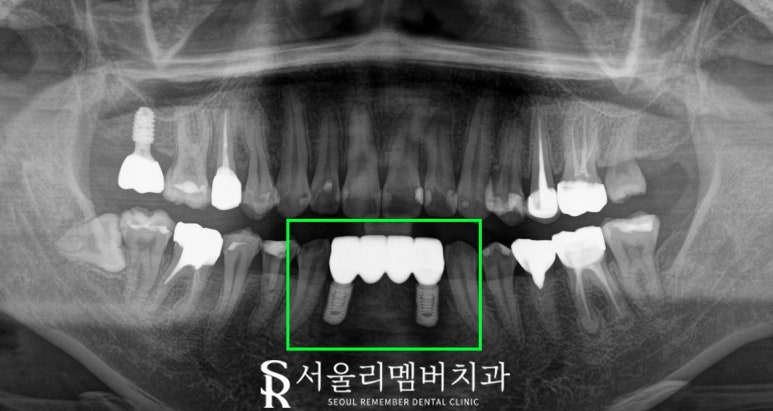

2개의 SOI. 픽스처를 식립한 뒤

상부 보철을 4개짜리 브릿지로 제작하여

3개월 만에 마무리된 모습입니다.

환자의 비용 부담을 줄이기 위해

심는 것은 2개만 심고

싱글 크라운이 아닌 브릿지로 제작하였습니다.

주변 치아들과 자연스럽게 어울릴 수 있도록

색도 신중하게 선택하였으며

치열도 고르게 만들어서

전보다 보기에도 좋네요.

바로 보이는 부위라

빠르게 마무리되는 것을

첫 번째로 중요하게 여기셨기에

오스템의 SOI를 활용했는데

그러길 잘한 것 같습니다.